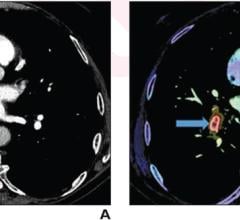

Advances in coronary CT angiography (CCTA) have reached the point where image quality and AI capabilities are creating ...

Feb. 4, 2026 — A new review published in the American Journal of Roentgenology (AJR) finds that advances in CT ...